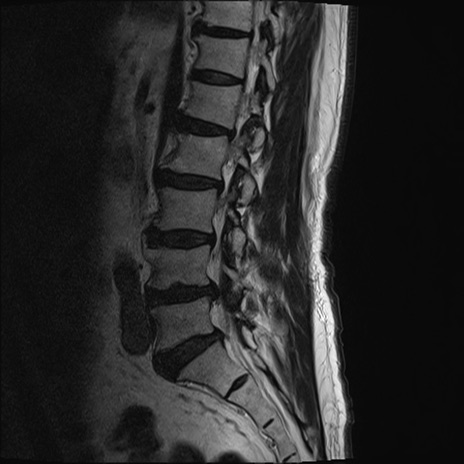

【整形】TIPS症例2 腰椎MRI T2WI(矢状断像)

【症例】70歳代男性

【主訴】左下肢痛

【現病歴】2週間前くらいから腰痛、左下肢痛あり。左臀部から大腿、下腿外側のしびれが常時ある。歩行とともに同部位の痛みあり。

【身体所見】Lasegue70-/60+、Bragard-/±、PTR ±/±、ATR -/-、IP 5/5、TA 5/4、TS 5/5、EHL 右第1足趾なし/3、FHL 5/5、hypersthesia(-)、足背動脈触知良好

異常所見と診断は?